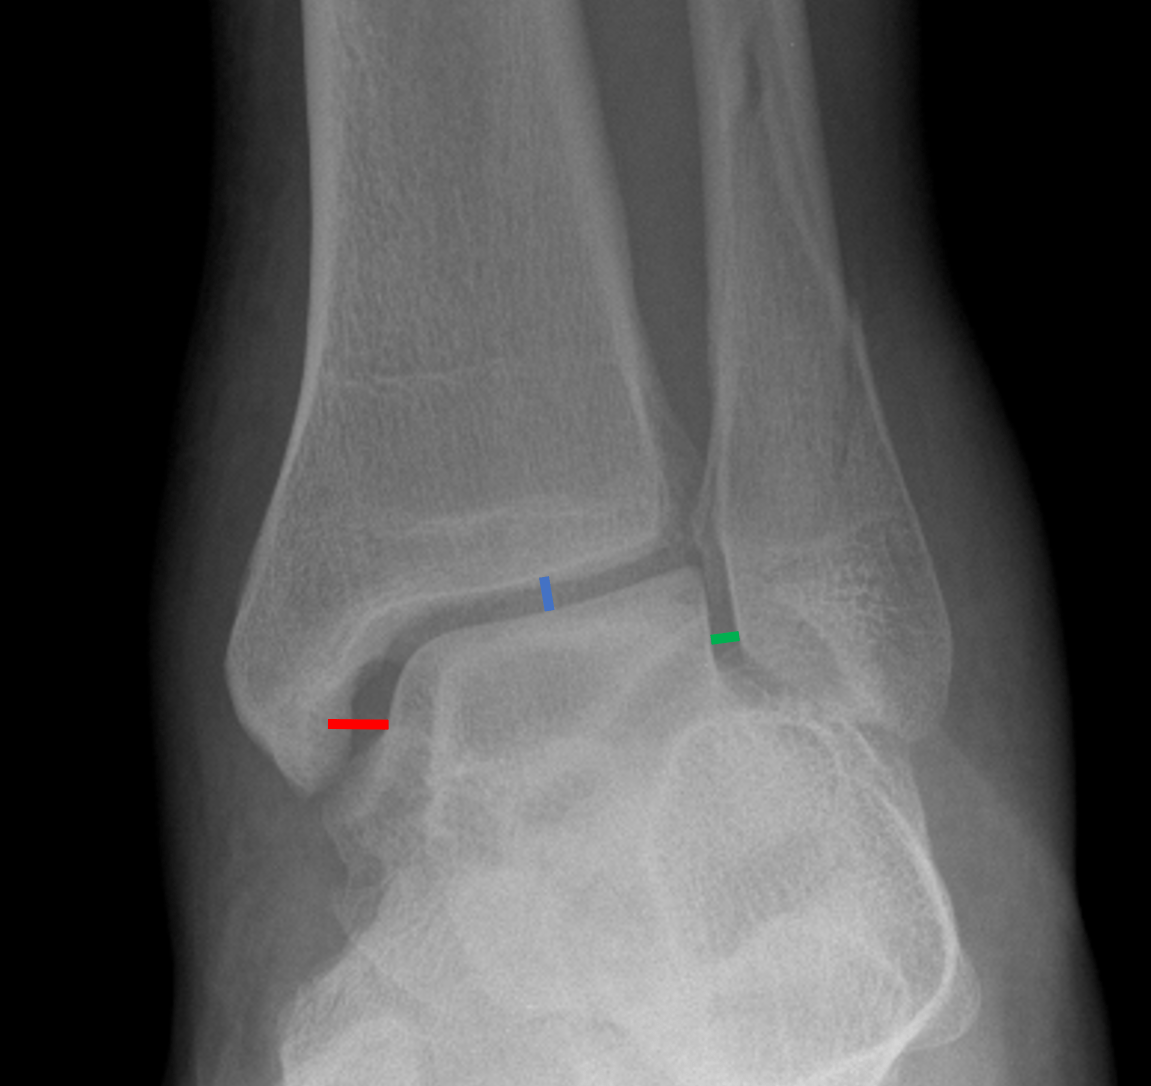

It is stabilized by three main ligaments: The anterior inferior tibiofibular ligament, the posterior inferior tibiofibular ligament, and the interosseous tibiofibular ligament, which are well delineated on magnetic resonance imaging. The tiba and fibula are the two main long bones of the lower leg.

Anterior and posterior proximal tibiofibular ligaments strengthen the joint capsule that runs in a superomedial direction from the head of the fibula to the tibial condyle. The proximal (superior) tibiofibular joint. Syndesmosis tibiofibularis [ta], distal tibiofibular joint , inferior tibiofibular joint , tibiofibular.

Where the bones to glide over one another to. Axial ct images at the level of the distal tibiofibular joint from (a) proximal to (d) distal (male, 53 years). Cartilagenous (or amphiarthosis) what type of joint is the symphysis pubis?

A Rough, Triangular Articular Area On The Medial Surface Of The Inferior End Of The Fibula Articulates With A Facet On The Inferior End Of The Tibia Distal Tibiofibular Joint: